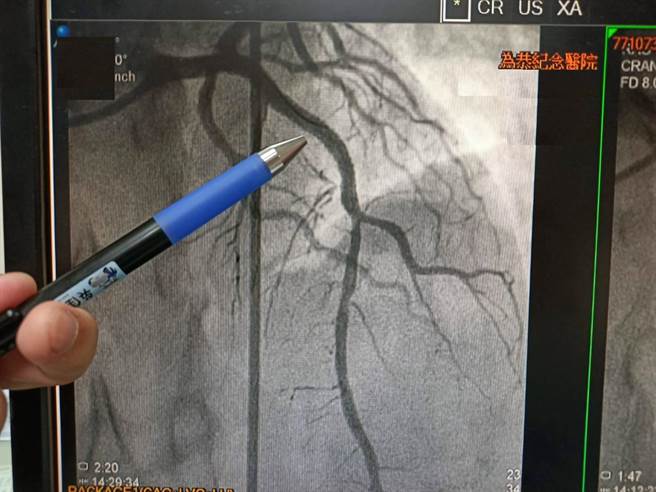

心导管放置支架后血液流通情形。(为恭医院提供/李京升苗栗传真)

日前一位43岁长期居住于头份市范先生,无慢性病史,突然严重胸痛,至重光医院急诊就医,检查后怀疑为急性心肌梗塞,经区域联防绿色通道转诊至为恭医院就诊,立即诊断为急性心肌梗塞,60分钟内紧急进行心导管治疗。